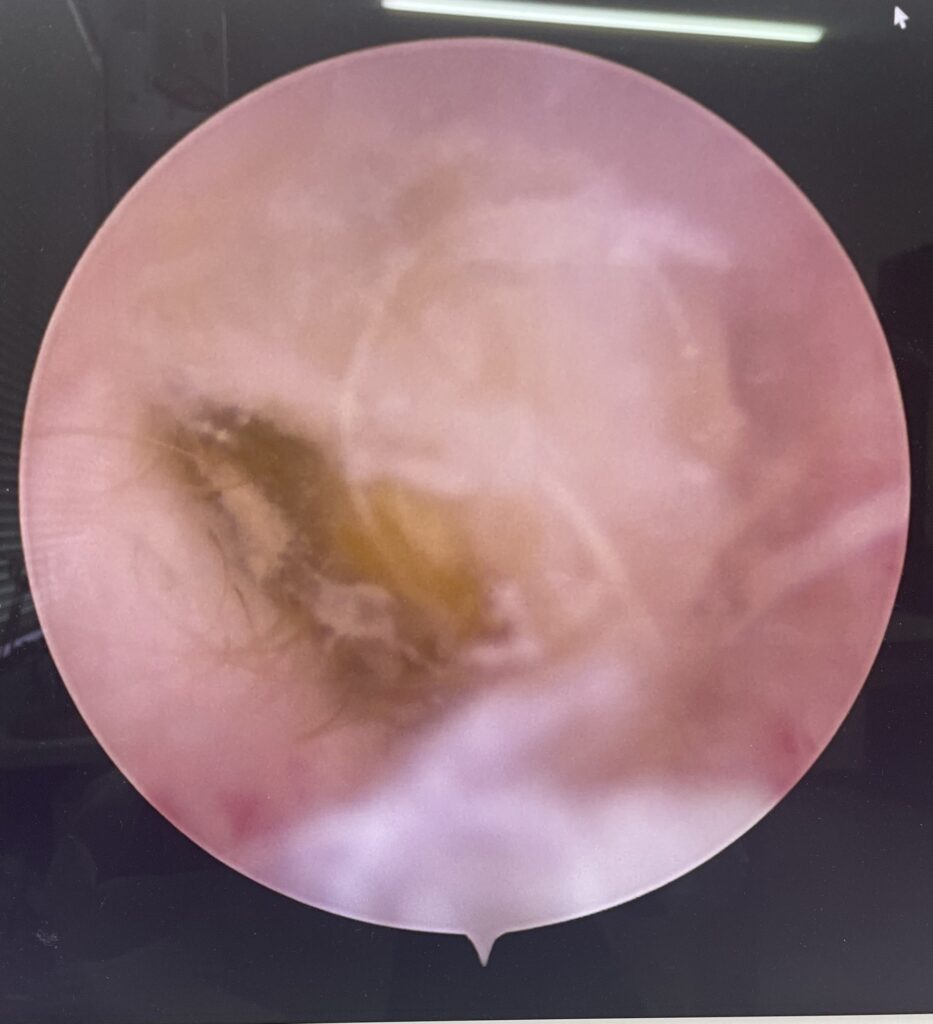

今までのオトスコープに比べて、できることも増えて、何より画質が格段に良くなりました📺

細かい汚れや変化がよく見えるようになったので、よりお耳を綺麗にできるようになりました✌